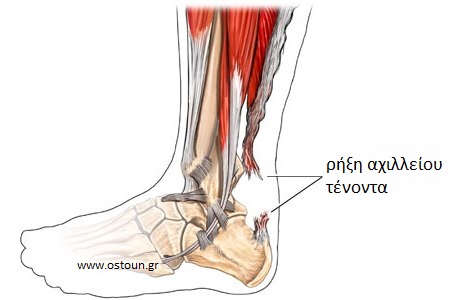

Η ρήξη του αχιλλείου τένοντα είναι η απότομη διακοπή της συνέχειάς του, με αποτέλεσμα την αδυναμία βάδισης. Ο αχίλλειος τένοντας είναι ο παχύτερος και ισχυρότερος τένοντας του ανθρωπίνου σώματος. Βρίσκεται στο οπίσθιο τμήμα του ποδιού μας, πίσω και πάνω από την πτέρνα. Μέσω του τένοντα αυτού καταφύονται στην πτέρνα ο γαστροκνήμιος και ο υποκνημίδιος μυς, οι οποίοι είναι πολύ βασικοί και χρήσιμοι στη βάδιση και στο τρέξιμο. Έχει υπολογιστεί ότι κατά το τρέξιμο στον αχίλλειο τένοντα ασκούνται δυνάμεις ίσες με το 8πλάσιο του βάρους μας, ενώ σε σπριντ μπορεί να φτάσουν και το 16πλάσιο!

Οι περισσότερες ρήξεις (75%) συμβαίνουν 2 με 6 εκατοστά πάνω από την κατάφυση του τένοντα στην πτέρνα. Η περιοχή αυτή διαθέτει σχετικά πτωχή αιμάτωση, γεγονός στο οποίο οφείλεται η σχετική αδυναμία του τένοντα να επουλώνει μικροτραυματισμούς και εκφυλιστικές αλλοιώσεις. Συνυπάρχουν πολλές φορές διαταραχές της ποιότητας του κολλαγόνου, στις οποίες παίζει ρόλο η κληρονομικότητα (χωρίς όμως να υπάρχει ομοφωνία μεταξύ των ερευνητών). Επί εδάφους αυτών των εκφυλίσεων των ινών του τένοντα, συμβαίνει το σχίσιμο του αχιλλείου κατά τη διάρκεια απότομης σύσπασης της γαστροκνημίας, όπως κατά τη διάρκεια άλματος, απότομης επιτάχυνσης, ή κατά την προσπάθεια αποφυγής μιας πτώσης.